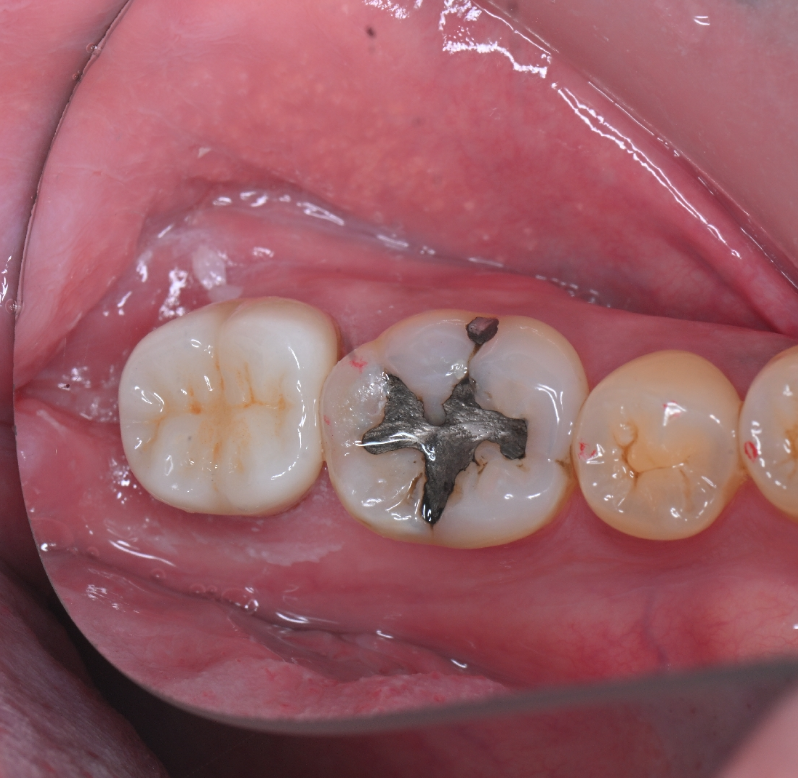

治療前の状態がこちらです。かみ合わせの面に金属の詰め物が入っています。

50代男性

治療回数:1回

Before